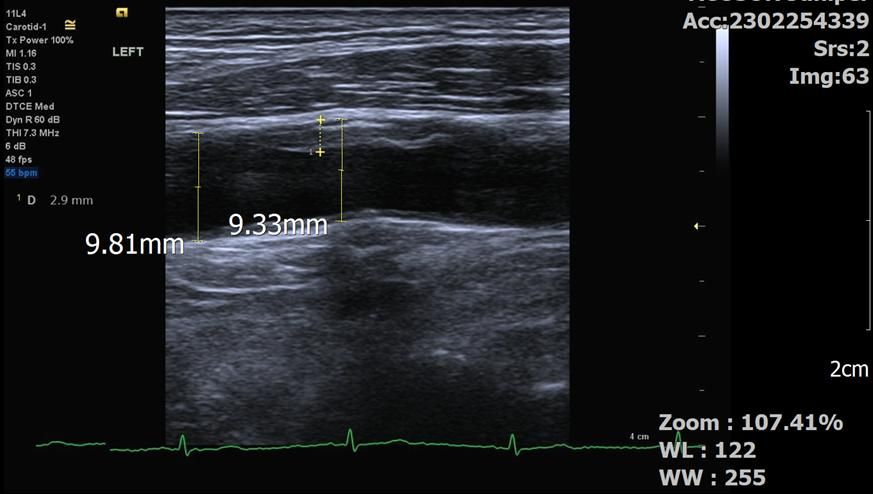

좌측 총경동맥입니다.

병원에서 재주신 플라크 사이즈는

CCA: 2.9 입니다.